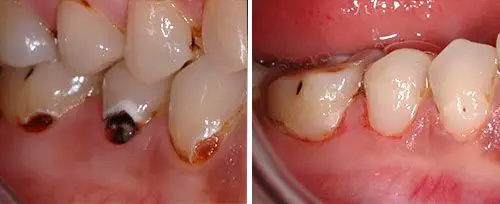

Carious Dentine Removal